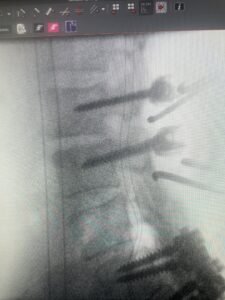

In this next case, this patient is a 47 year-old female who presents with intractable low back pain with severe pain, numbness, and weakness in the right lower extremity that had gotten progressively worse over a year. The patient had failed conservative management including physical therapy and epidurals. She was noted to have ⅘ weakness of plantar flexion. MRI demonstrated a large right L5-S1 disc herniation with severe compression of the descending right S1 nerve root (Fig 3). It was decided to perform a right L5-S1 hemilaminectomy for removal of the disc fragment and decompress the S1 nerve root. When you expose the disc, one must be certain to release any anterior adhesions to the nerve root in order to prevent a dural tear during retraction of the nerve root. It is also important to make sure during exposure and you finally encounter the dura after removing the ligamentum and fat, to make sure you are looking at the nerve root and not the main trunk of the thecal sac because if you don’t you can avulse or damage the nerve root if you retract the wrong structure.

Fig. 3a: Sagittal and axial T2-weighted lumbar MRI images demonstrating large right L5-S1 disc herniation (red arrows)